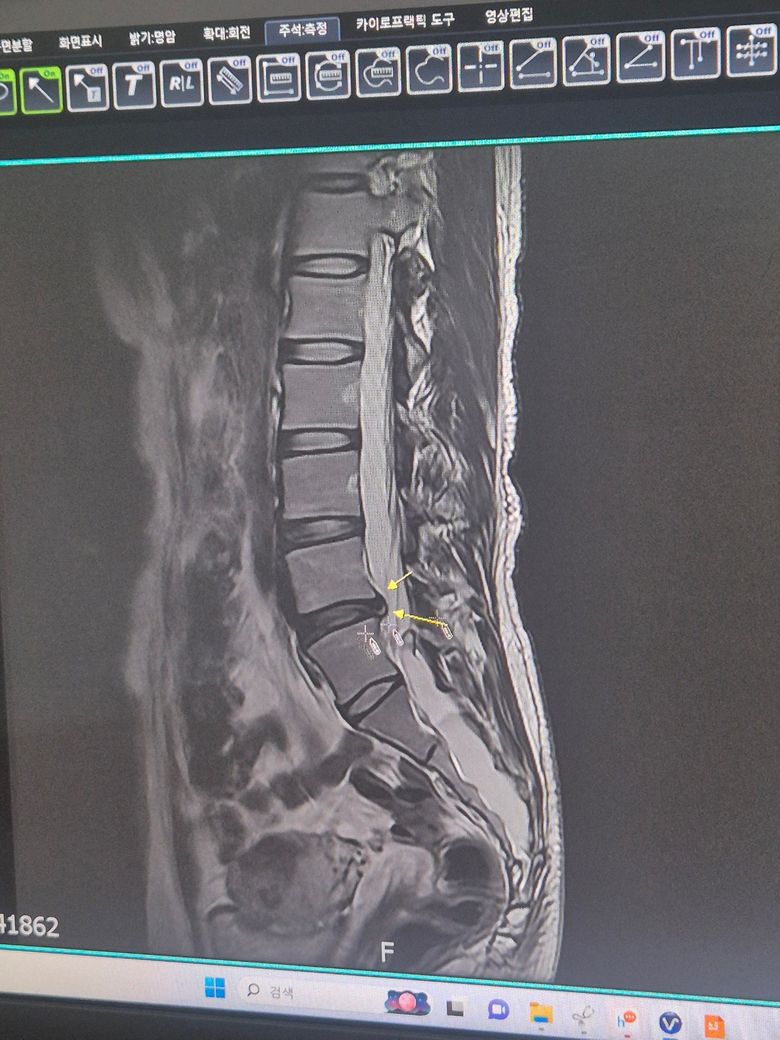

MRI상 현재 허리 아래쪽 L4~L5 디스크가 뒤쪽으로 돌출되어 있는 것으로 보이며 신경 지나가는 공간 쪽을 살짝 누르는 것으로 보이며 초기에서 중등도 허리디스크일 가능성이 높습니다.

사진상으로는 디스크가 살짝 뒤로 튀어나온 “초기~중등도(돌출/팽윤 단계)“보이며, 심한 탈출 단계로 보이진 않습니다.

현재 사진상 요추 4-5번 사이의 디스크가 뒤쪽으로 돌출된 디스크 탈출 단계로 보이며 , 노란 화살표가 가르키는 부분이 신경통로를 압박하고 있습니다. 다행히 저린 증상이 없다는건 신경뿌리가 완전히 눌리기 전이거나 감각신경위주로 자극받은 상태일수 있습니다. 현재 통증이 심하므로 약물치료,물리치료,주사치료를 통해 염증과 부종을 먼저 가라앉히는데 우선입니다.